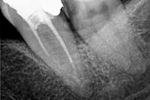

Revisionsbehandlung eines Unterkiefermolaren (37) vor geplanter Überkronung (Dr. Maik Göbbels) Download